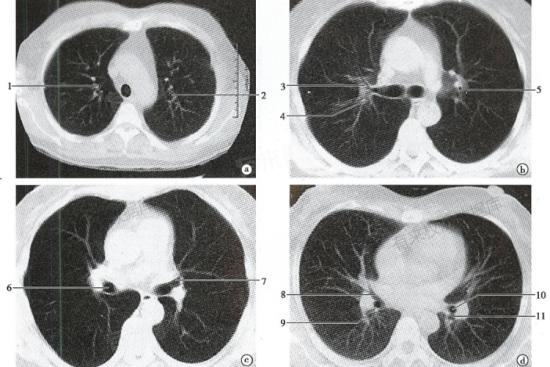

2、肺部CT的局限性:肺部CT是一种影像学检查方法,虽然能够发现大多数肺部异常,包括肺癌,但对于一些特别小的肿瘤或早期肺癌,可能存在漏检的情况。这意味着即使CT结果显示正常,也不能完全排除肺部存在微小病变的可能性。